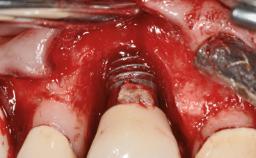

A 24-year-old female patient was treated with an implant- supported crown for single-tooth replacement at site 11. A Straumann Bone Level RC implant (Institut Straumann AG, Basel, Switzerland) was placed with simultaneous bone augmentation, and the periimplant emergence profile was conditioned with a fixed implant-supported provisional crown. After finalization of the mucosal architecture, the clinical situation was transferred by means of a custom impression post for fabrication of an implant-supported screw-retained onepiece crown consisting of a CARES® zirconia abutment (Straumann) with a direct ceramic veneer.